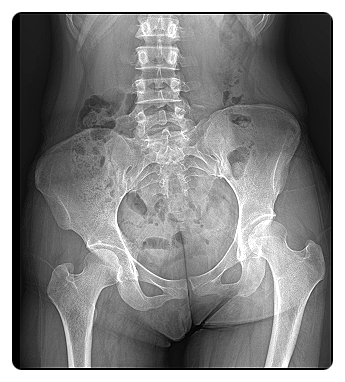

고관절은 몸의 중심에 위치한 큰 관절로, 상체와 하체를 이어주는 핵심적인 역할을 합니다.

때문에 고관절에 문제가 생기면 단순히 관절만이 아니라, 골반과 허리, 다리 전체의 움직임에도 영향을 미칩니다.

특히 통증이 남아 있는 경우, 고관절 주변 근육의 긴장과 부정렬된 체형이 원인인 경우가 많습니다.

근육의 균형이 깨지면 관절이 제자리에서 움직이지 못해, 작은 움직임에도 불편감이 커지게 됩니다.